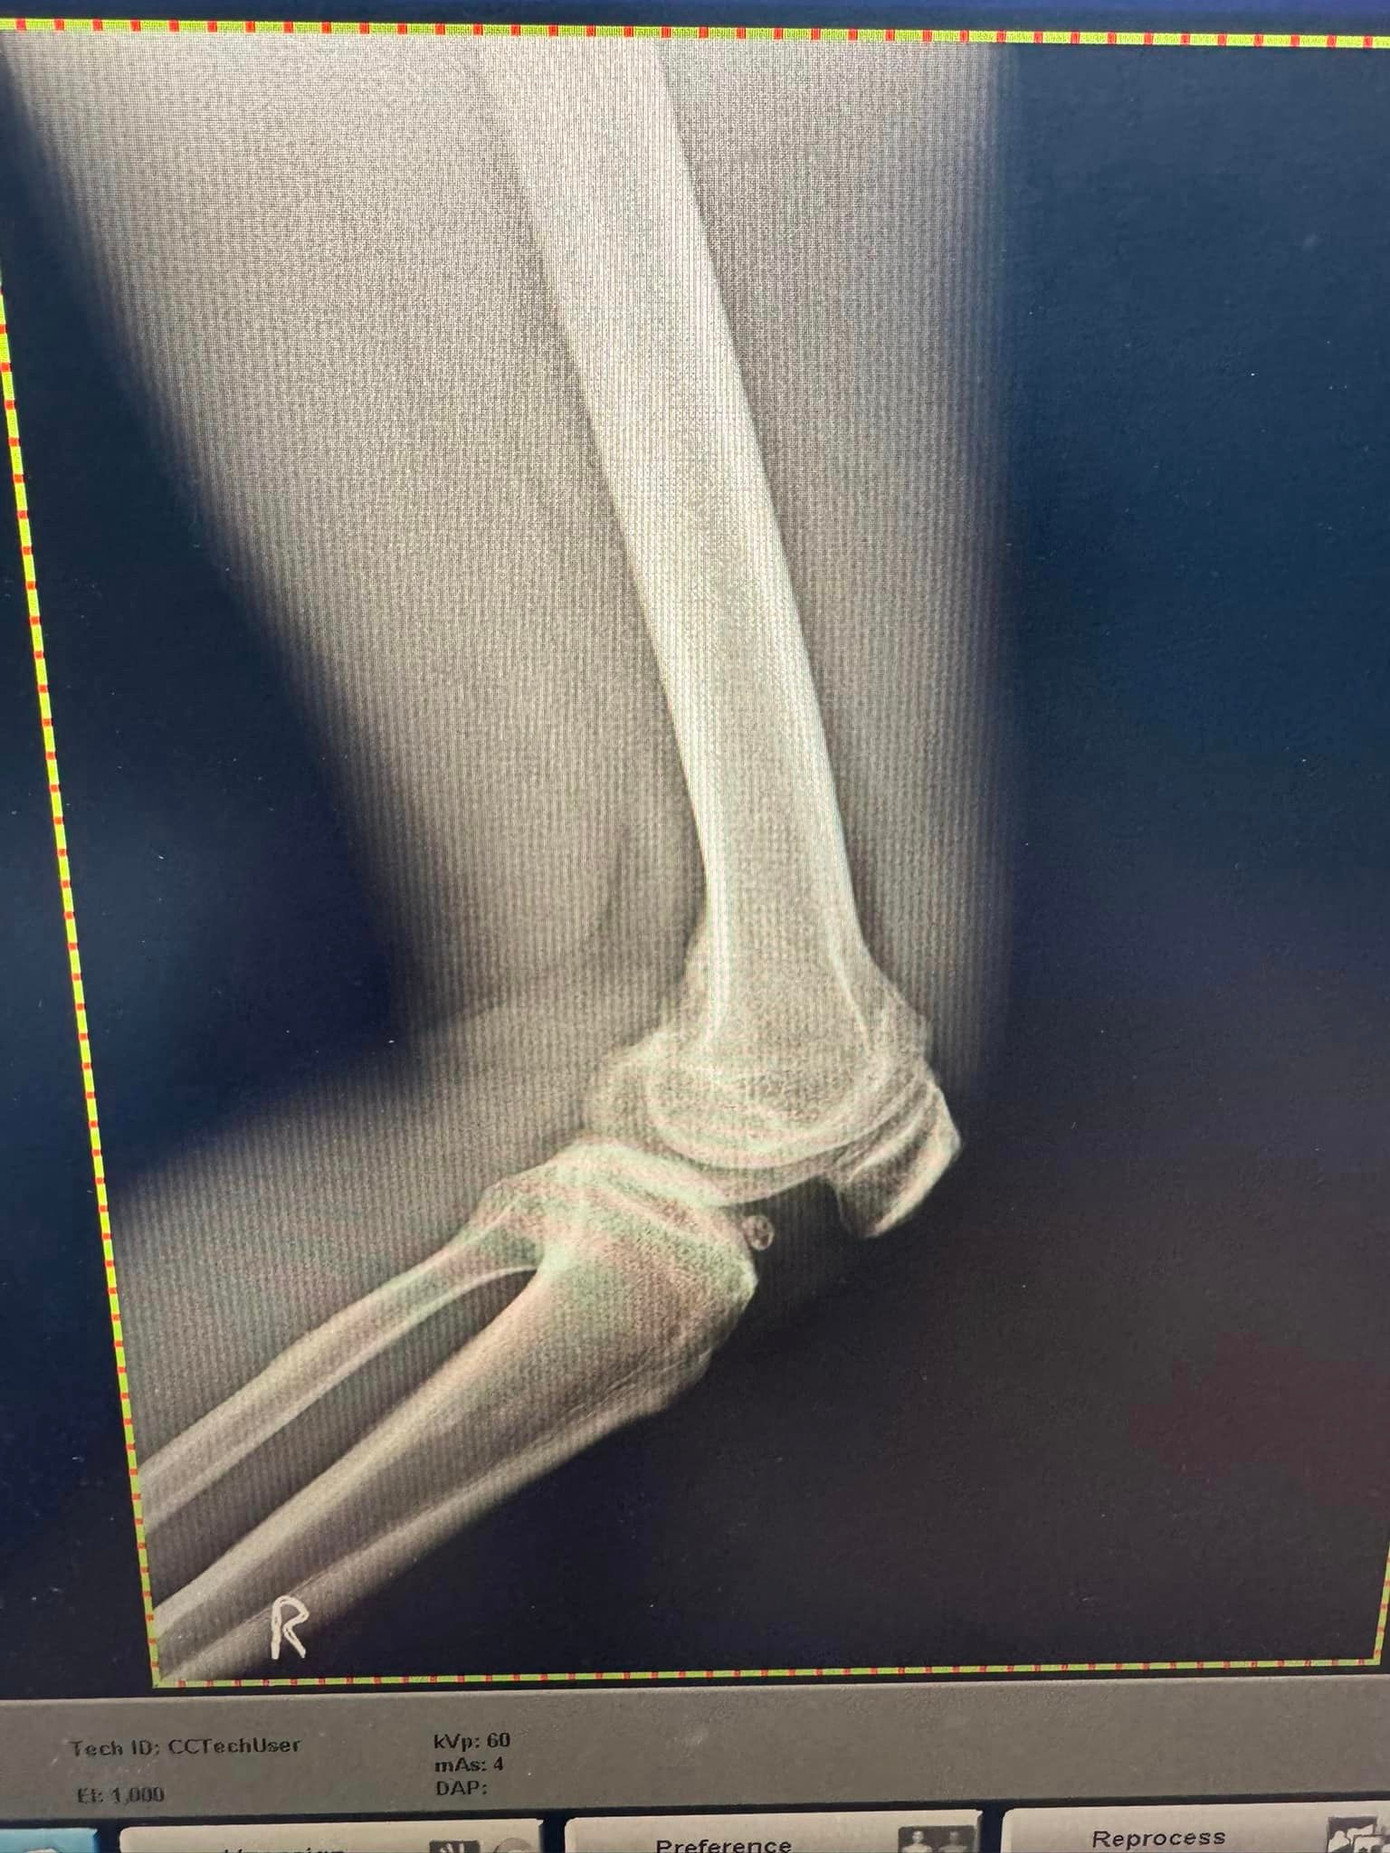

Theo hình ảnh Tuấn Hưng chia sẻ, nam ca sĩ gặp chấn thương khá nghiêm trọng. Anh được bác sĩ chỉ định hạn chế vận động. Tuy nhiên, Tuấn Hưng nói anh vẫn lạc quan.